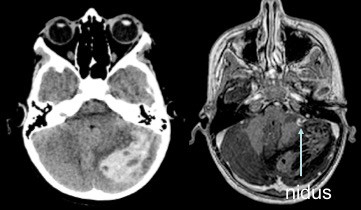

MAV cérébelleuse

les MAV cérébelleuses sont particulièrement dangereuses et sont au premier rang de la mortalité par saignement de MAV.

il s’agit donc d’une indication de chirurgie urgente, sans attendre la dégradation neurologique qui est brutale.

l’imagerie injectée (angioscanner ou comme ici ARM) permet de localiser le nidus par rapport à l’hématome.

opératoirement, devant un cervelet tendu, il est souvent illusoire de tenter de contrôler les pédicules avant d’évacuer l’hématome, cette évacuation est alors le premier temps de l’abord du nidus, qui est ensuite contrôlé en isolant progressivement les afférences artérielles à sa périphérie et en terminant par le drainage veineux.

ici, le saignement opératoire est plus lié aux veines cortico-durales et aux sinus veineux duraux sous pression qu’à la MAV elle-même.

dans certains cas, où les pédicules sont volumineux et le drainage peut être contourné, on parvient à réaliser un contrôle exsangue de la malformation.